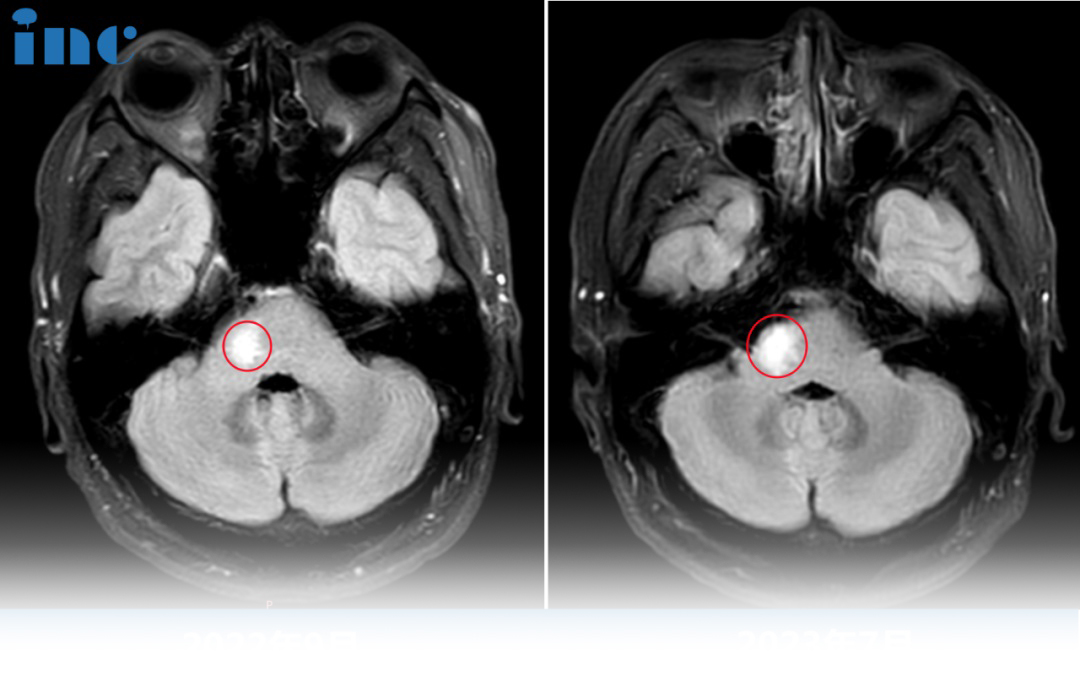

34岁男性--脑干延髓胶质瘤

34岁男性--脑干延髓胶质瘤,短短的6个月,林先生的症状越发严重,左侧颈部,肩部,上肢僵硬紧绷,吞咽时左侧咽喉部紧绷,有轻度阻碍感,左上肢轻度麻木……医生建议手术,但因为手术风险大,他们做不了,有长期插管的风险……“如果巴教授做手术,切除率是多少?”

巴教授评估回复

切除率很可能是全切或接近。近期,我为一位女士做了一个类似的手术,临床效果好,肿瘤被完全切除(该患者术后3个月时已证实)。由于病理与目前的病例相似,我很肯定在这里也能取得同样的结果。

2023年6月中国行期间,巴教授为这名高难度延髓肿瘤患者顺利全切,术后无任何新发神经损伤,术后一天意识清醒,四肢活动正常、言语呼吸吞咽功能正常。术后一个多月,患者行走自如已基本恢复正常生活。